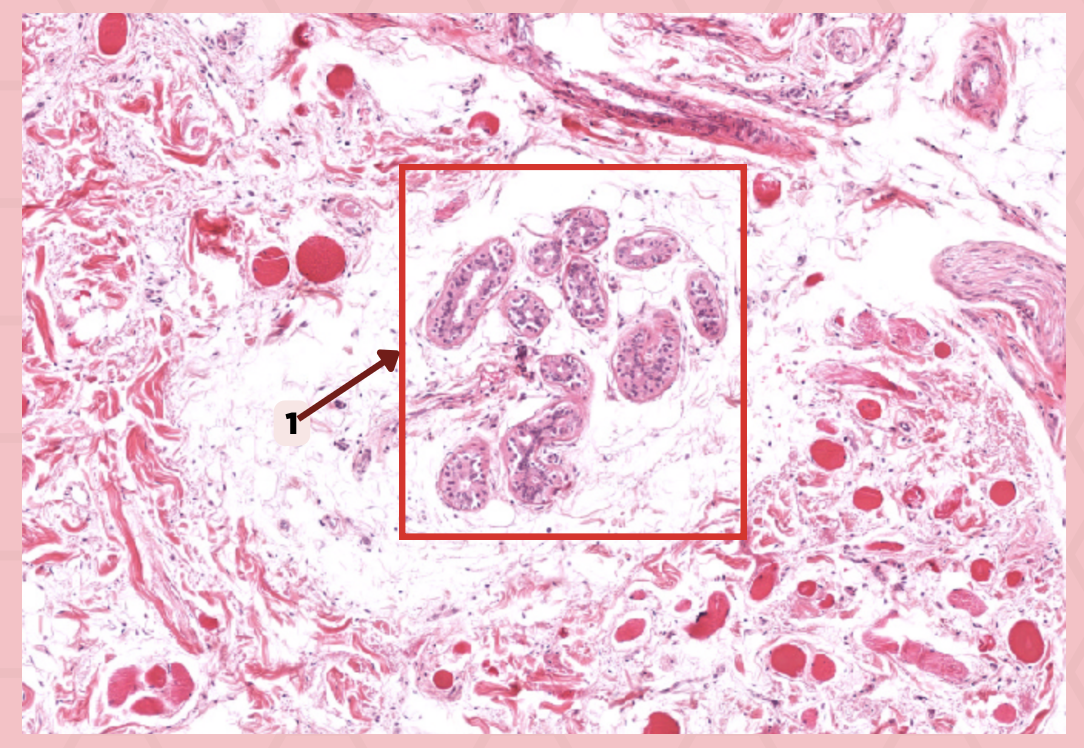

Lip

What specimen is showed in the picture?

Labial Glands (in the Mucosa)

Identify the structure labeled as 1.

Skeletal Muscle Cells

Identify the structure labeled as 2.

Lamina Propria

Identify the structure labeled as 3.

Mucosa

Identify the structure labeled as 4.

Lip

What specimen is showed in the picture?

Skeletal Muscle Fibers

Identify the structure labeled as 1.

Labial Glands

Identify the structure labeled as 2.